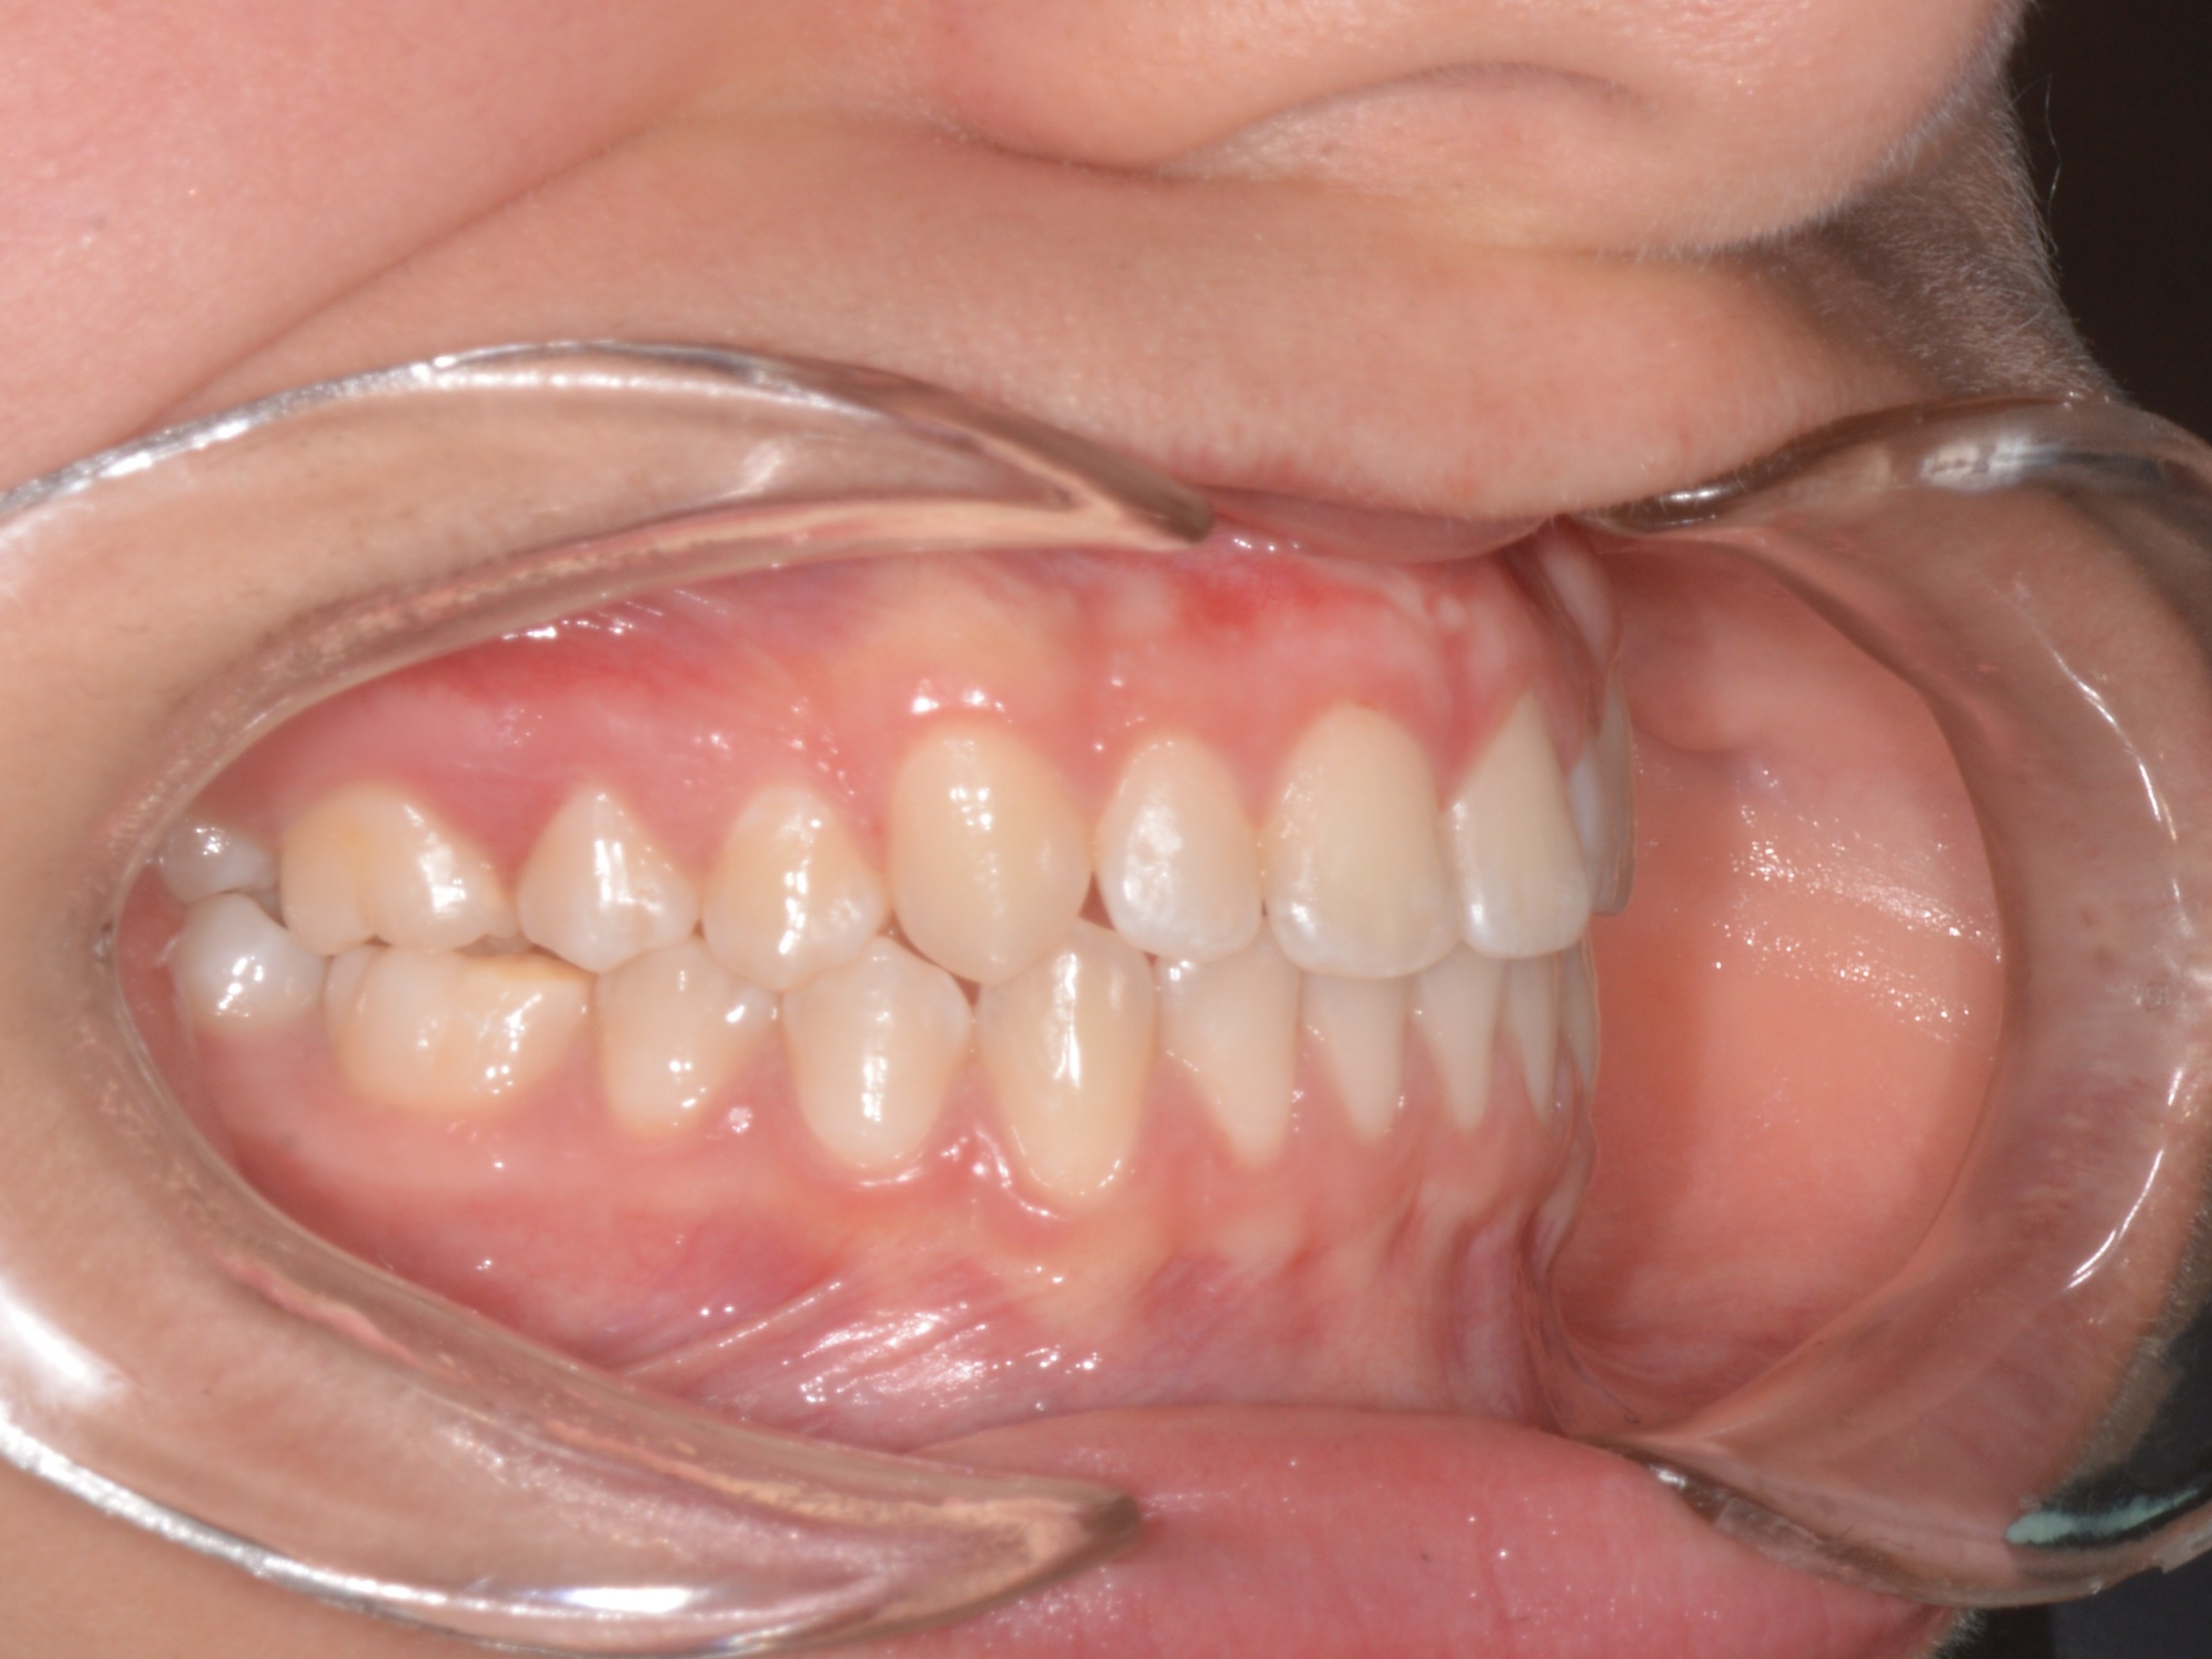

Femmina, 13 anni

Classe III

• Diastema

• Deviazione della linea mediana mascellare

• Archi stretti

• Morso aperto